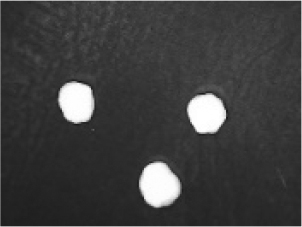

In addition to the disintegration endpoint studied using the USP disintegration apparatus, the pellets disintegrated into particles of various sizes when evaluated at a static position. A few drops of water were placed on the pellets on the opaque surface. A USB digital microscope (China) was connected to a computer to capture the disintegration process. Images were captured from the beginning until the pellet disintegrated or exploded into small fragments. Pellet images were acquired every 30 seconds. for formulations containing polyplasdone XL 10 and croscarmellose sodium.

Disintegration was evaluated at room temperature under static conditions. The camera captured images every 30 s ( Table 9), illustrating that MCC pellet X3 with mannitol and PEG 400 did not disintegrate. Within 120 s, cracks appeared in P5 pellets containing mannitol, PEG, and PPXL. As seen in the C4 pellets, they begin to explode into many fragments within 30 s. Moreover, the CP12 pellets containing PEG 400, mannitol, CCS, and PPXL began to explode into many loosely linked particles after 60 s, which quickly separated under the oscillating motion of the USP disintegration equipment. The photographs are compatible with the results mentioned above for the USP disintegration device. When the temperature was increased to 37°C, the disintegration caused the split into tiny fragments.

Table 9. Camera capture of pellet disintegration at different time intervals.

Pellet # 0 sec. 30 sec. 60 sec. 90 sec. 120 sec.

X3c9c3975f-9288-4951-a800-a8e9fc463382_GRA58.gif c9c3975f-9288-4951-a800-a8e9fc463382_GRA59.gif c9c3975f-9288-4951-a800-a8e9fc463382_GRA60.gif c9c3975f-9288-4951-a800-a8e9fc463382_GRA61.gif c9c3975f-9288-4951-a800-a8e9fc463382_GRA62.gif

P5c9c3975f-9288-4951-a800-a8e9fc463382_GRA63.gif c9c3975f-9288-4951-a800-a8e9fc463382_GRA64.gif c9c3975f-9288-4951-a800-a8e9fc463382_GRA65.gif c9c3975f-9288-4951-a800-a8e9fc463382_GRA66.gif c9c3975f-9288-4951-a800-a8e9fc463382_GRA67.gif

C4c9c3975f-9288-4951-a800-a8e9fc463382_GRA68.gif c9c3975f-9288-4951-a800-a8e9fc463382_GRA69.gif c9c3975f-9288-4951-a800-a8e9fc463382_GRA70.gif c9c3975f-9288-4951-a800-a8e9fc463382_GRA71.gif c9c3975f-9288-4951-a800-a8e9fc463382_GRA72.gif

CP12c9c3975f-9288-4951-a800-a8e9fc463382_GRA73.gif c9c3975f-9288-4951-a800-a8e9fc463382_GRA74.gif c9c3975f-9288-4951-a800-a8e9fc463382_GRA75.gif c9c3975f-9288-4951-a800-a8e9fc463382_GRA76.gif c9c3975f-9288-4951-a800-a8e9fc463382_GRA77.gif

CPP4c9c3975f-9288-4951-a800-a8e9fc463382_GRA78.gif c9c3975f-9288-4951-a800-a8e9fc463382_GRA79.gif c9c3975f-9288-4951-a800-a8e9fc463382_GRA80.gif c9c3975f-9288-4951-a800-a8e9fc463382_GRA81.gif c9c3975f-9288-4951-a800-a8e9fc463382_GRA82.gif

CPO4c9c3975f-9288-4951-a800-a8e9fc463382_GRA83.gif c9c3975f-9288-4951-a800-a8e9fc463382_GRA84.gif c9c3975f-9288-4951-a800-a8e9fc463382_GRA85.gif c9c3975f-9288-4951-a800-a8e9fc463382_GRA86.gif c9c3975f-9288-4951-a800-a8e9fc463382_GRA87.gif

The CP12 pellet disintegration process is depicted in the video in the supplementary material (refer to underlying data). The pellets swelled immediately before exploding and quickly disintegrating. The orphenadrine citrate pellets began to swell and cracks appeared after 120 s, which were easily separated under the oscillating motion of the USP disintegration equipment. The photographs are compatible with the results of the USP disintegration device. When the temperature was increased to 37°C, disintegration caused the fragments to split into smaller fragments. When the temperature was increased to 37°C, disintegration caused the split into tiny fragments. The pseudoephedrine hydrochloride pellets began to explode into several pieces of loosely linked particles within 120 s, which were easily separated by the oscillating motion of the USP disintegration equipment. The photographs were compatible with the results obtained from the USP disintegration device. When the temperature increased to 37°C, the disintegration caused the split into tiny fragments. Although this is not an official USP test, using video capture for disintegration validates Chamsai’s claim of quick disintegration.18